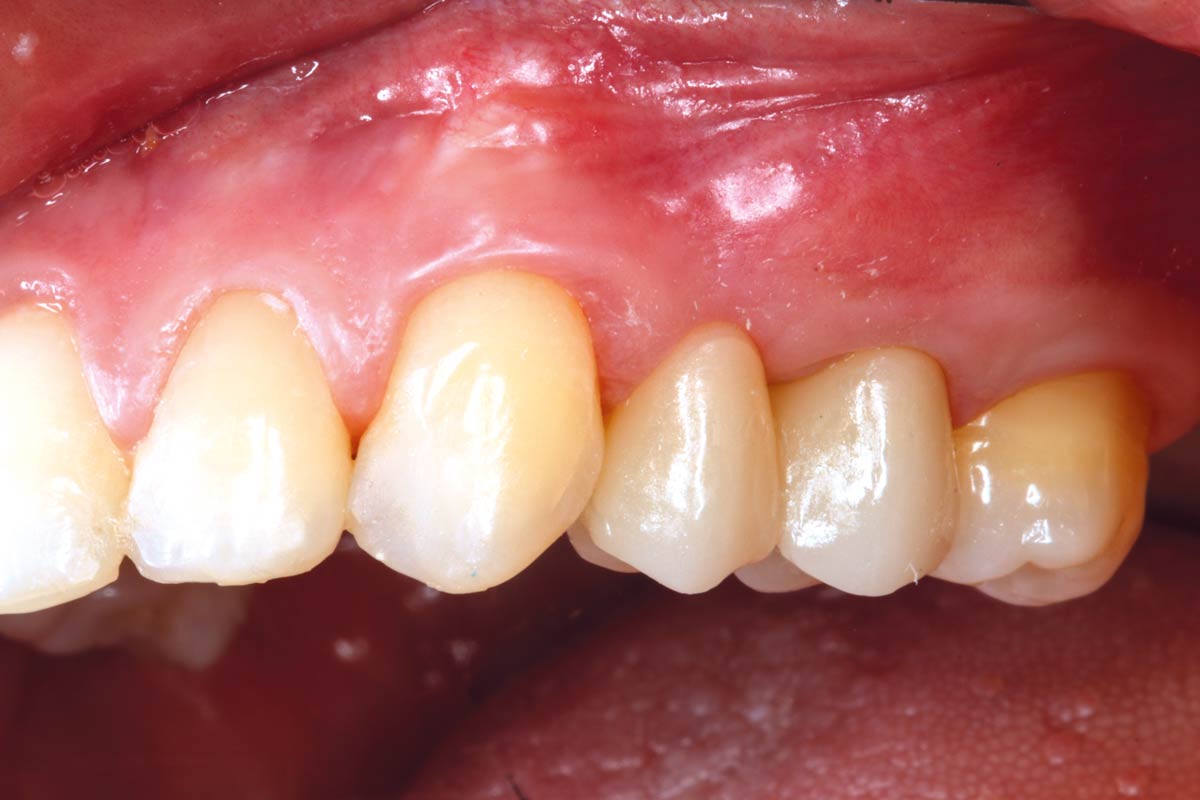

Gingival recession at tooth 13. Free gingival graft (FGG) of a previous surgery for root coverage visible.